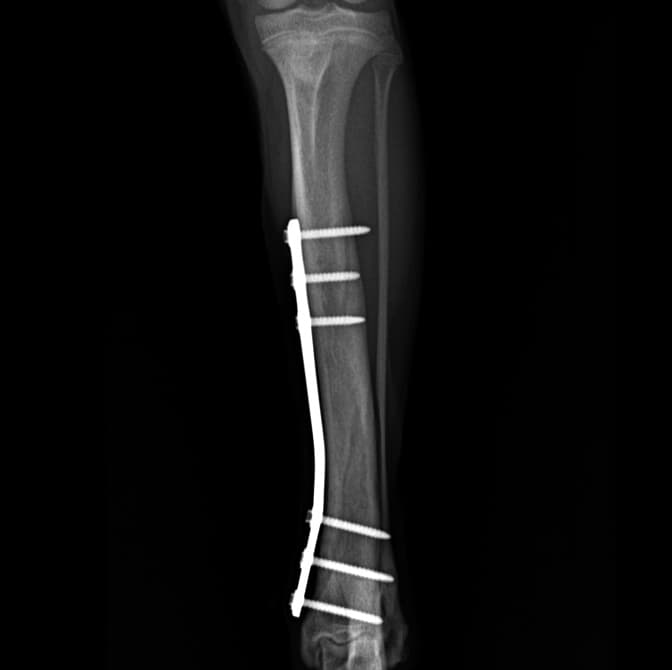

정형외과 전공의 수의사가 직접 수술합니다.

02C-arm을 통해서 좀 더 섬세한 정형외과 수술을 진행하고, 본원에서는 외과적 침습을 최소화 하는 중재적 시술 (기관 협착, 동맥관개존증(PDA), SUB 등)을 진행하고 있습니다.

11유명한 Stryker사 장비. 골절 수술, 절골등 다양한 정형/신경외과 수술시 사용

12정교한 정형외과 도구를 사용하여 신속 정확한 정형외과 수술이 가능

13수술 중 골절 상태 혹은 이식물 적용 후 상태 등 육안으로 명확히 확인하기 힘든 상태를 X-ray 확인하여 정확한 수술 결과를 만들어 내는 것이 가능